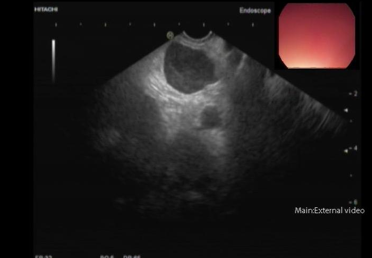

这项技术就像给身体内部做"精准定位的微创探查",医生通过带有超声探头的特殊内镜,配合比圆珠笔芯还细的穿刺针(直径约1毫米),在体内GPS导航般的精准定位下,安全获取深层组织的细胞样本。

2. 超声内镜精确定位病灶

3. 微型穿刺针精准取样(3-5次/部位)